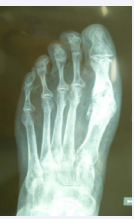

We report on a 63 year-old female patient undergoing treatment for Müller-Weiss disease and metatarsalgia due to hallux valgus-rigidus, unrelated to the talonavicular joint pathology. She underwent surgery in October 2013, when Toefit-Plus MTP prosthesis was implanted (Figure 1).

Figure 1: Immediate post-operative dorsal-plantar radiographic image of the Toefit- Plus prosthesis.